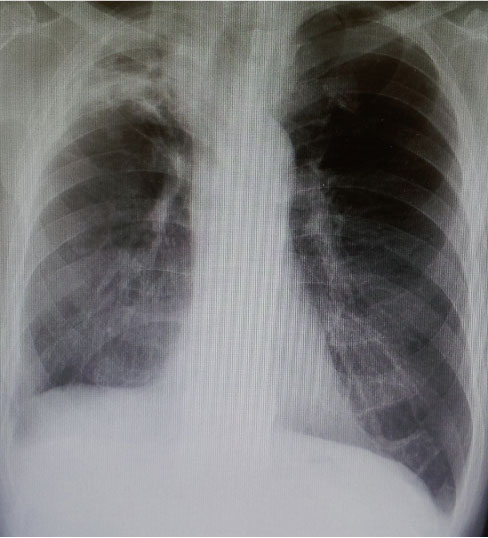

<‰æ‘œŠŒ©>

@E‹¹•”XpF’‹Œ«”xŒ‹Šj‹^‚¢